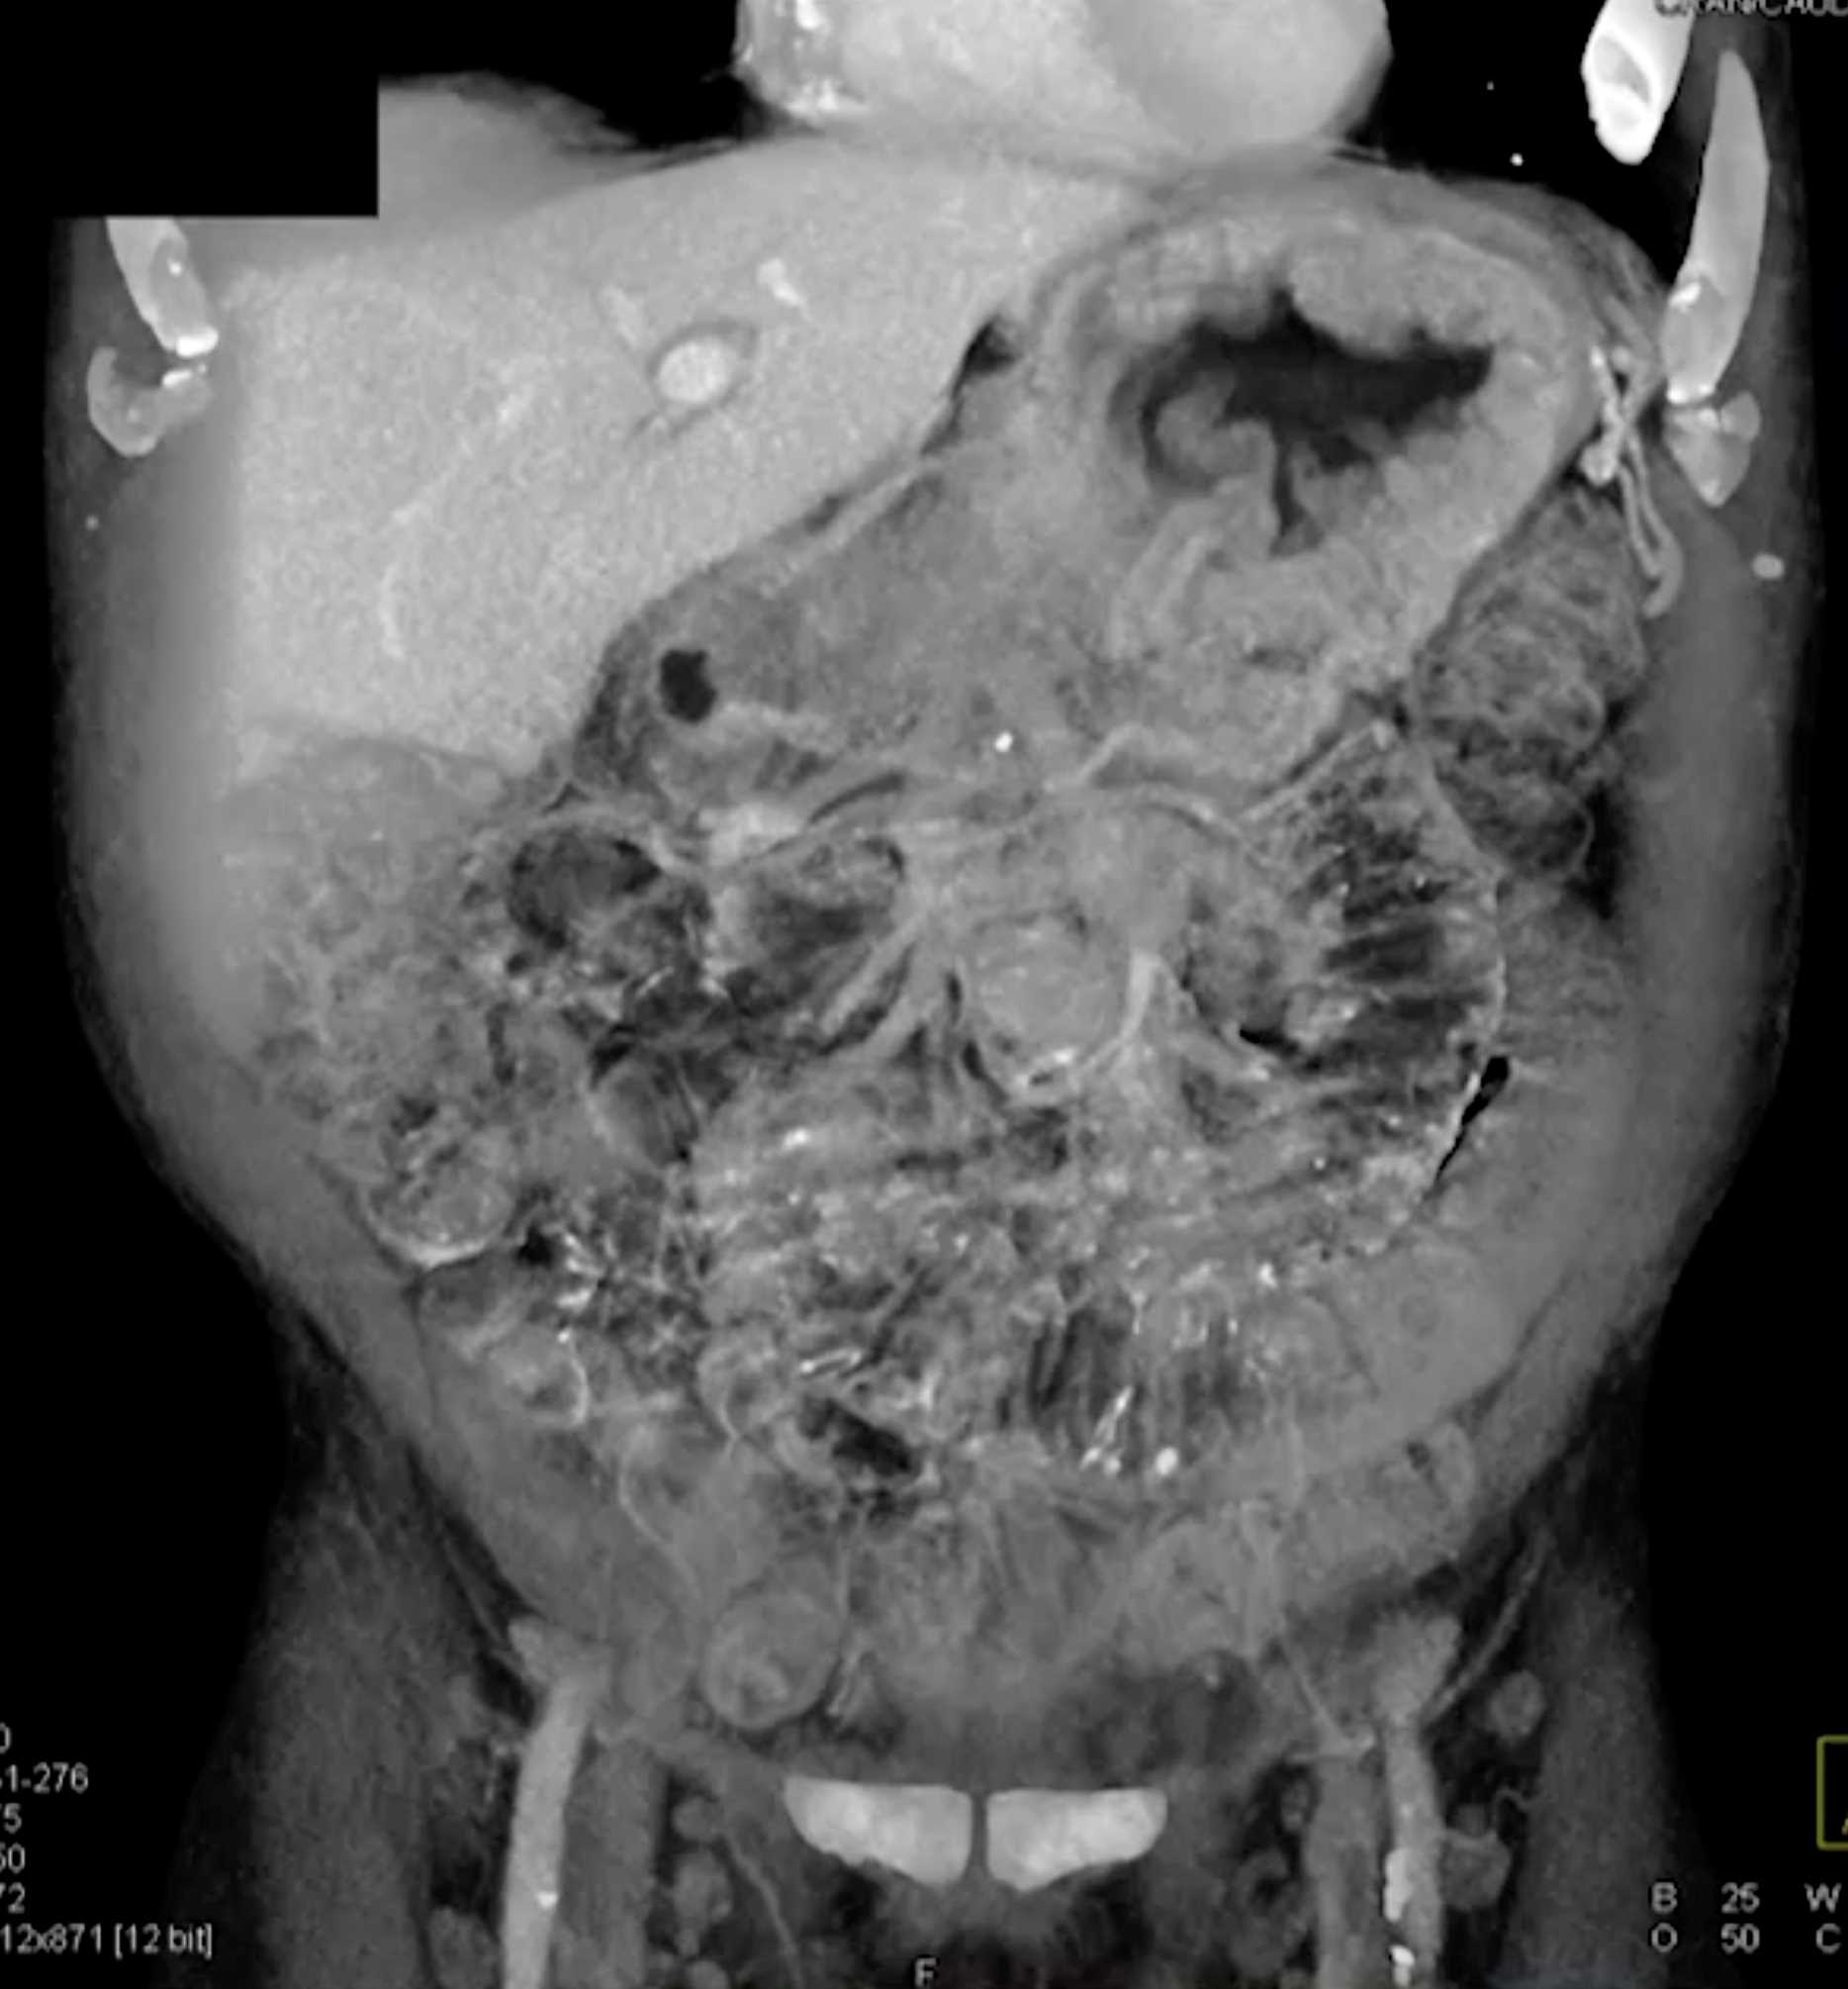

Chemical Gastritis due to NSAIDs